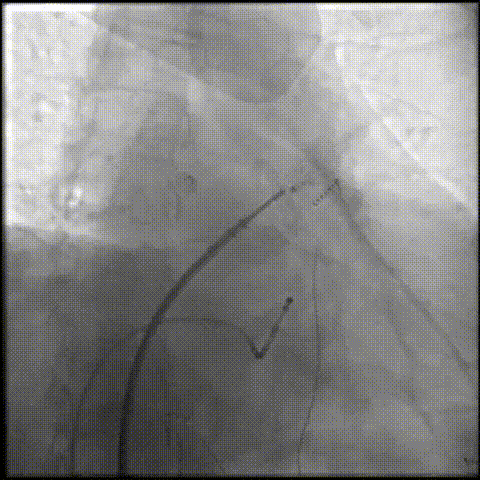

右肩位造影测量锚定区:19.3mm,开口部:25.6mm。

右肩位造影

肝位造影测量锚定区:21.2mm,开口部:27.1mm。选择LAMax LAAC® 2430 Normal型号左心耳封堵器。

肝位造影

锚定伞锚定在主干区域,再将封堵盘逐渐打开,保证封堵效果,封堵盘完全打开后造影,外盘覆盖外口,封堵完全,无残余分流。

封堵伞打开

封堵盘打开后造影